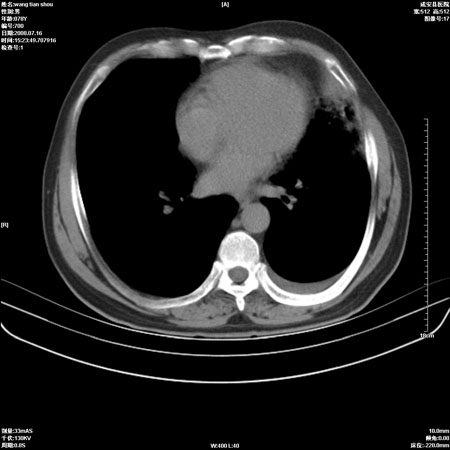

以下是引用qingjing在2008-7-16 19:55:00的发言:[br]1、左上肺不张并堵塞性炎症,建议支气管镜详查;[br]2、左侧胸腔少量积液。

以下是引用wzr在2008-7-16 20:26:00的发言:[br]左肺肺不张伴阻塞性肺炎!另:左侧胸腔少量积液。建议纤支镜检查!